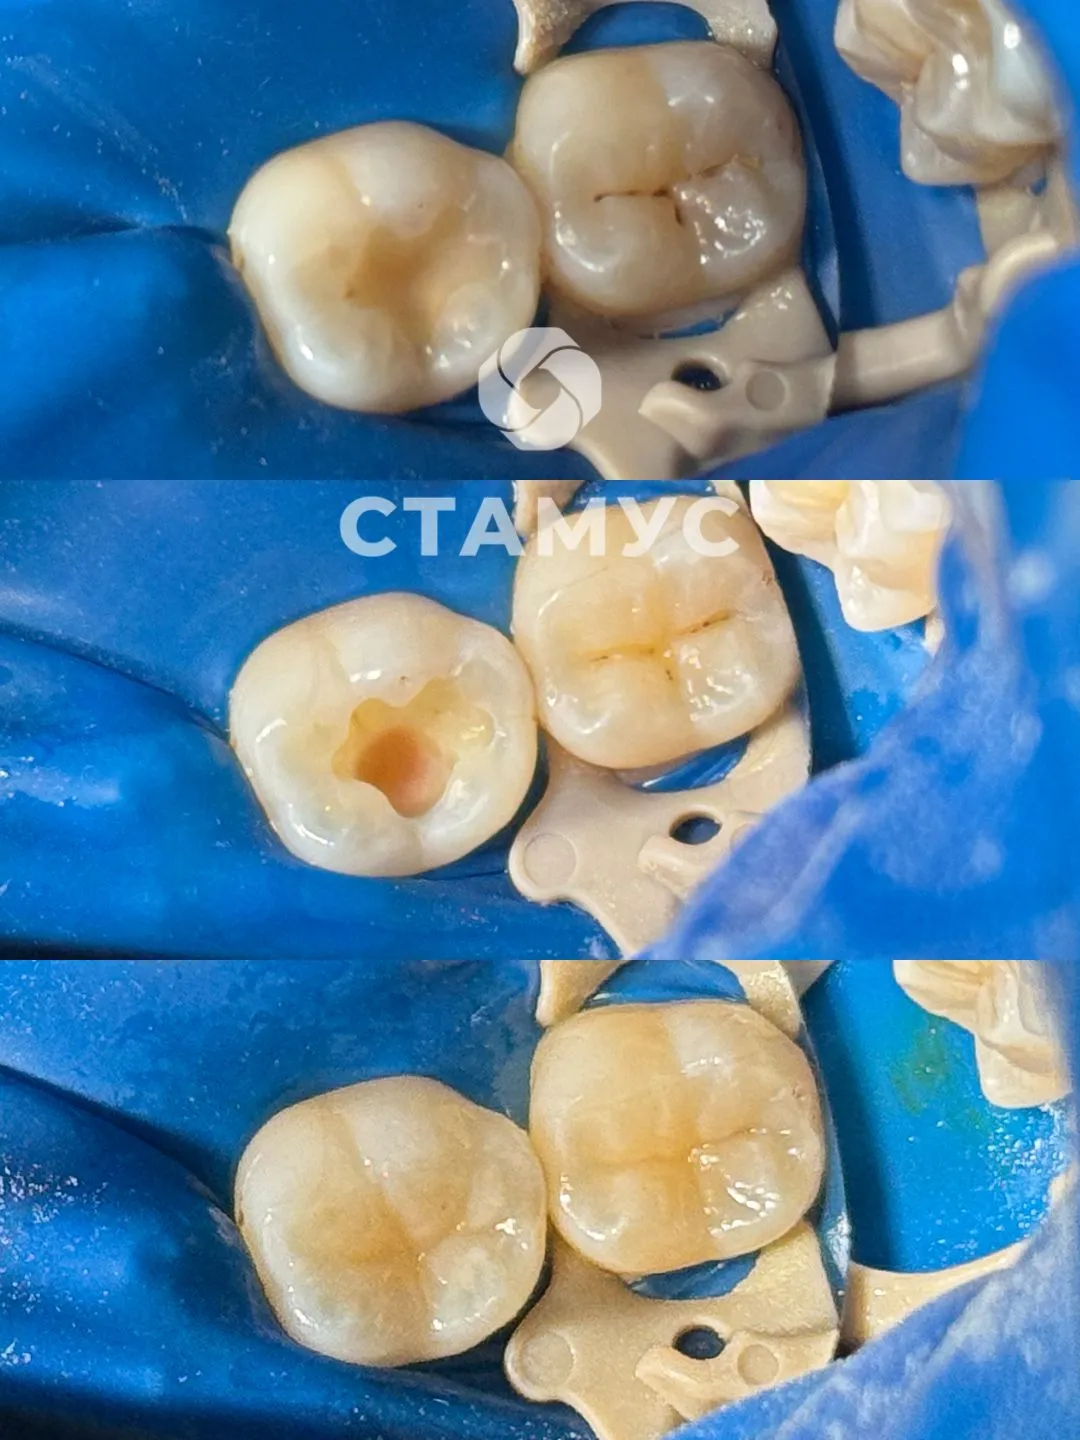

Лечение кариеса

Чувствительность зубов на кислые раздражители.

Проведено лечение зубов 36 и 37.